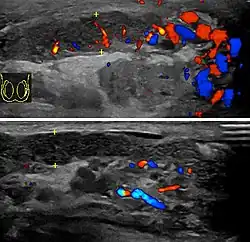

Scrotal ultrasound showing calcifications and cysts in a case of chronic epididymis.

Chronic epididymitis is a form of epididymitis that persists for more than three months. Chronic epididymitis is characterized by inflammation even when there is no infection present. Tests are needed to distinguish chronic epididymitis from a range of other disorders that can cause constant scrotal pain, including testicular cancer (though this is often painless), enlarged scrotal veins (varicocele), calcifications,[15] and a possible cyst within the epididymis. Some research has found that as much as 80% of visits to a urologist for scrotal pain are for chronic epididymitis.[4]: p.311  As a further complication, the nerves in the scrotal area are closely connected to those of the abdomen, sometimes causing abdominal pain similar to a hernia (see referred pain).